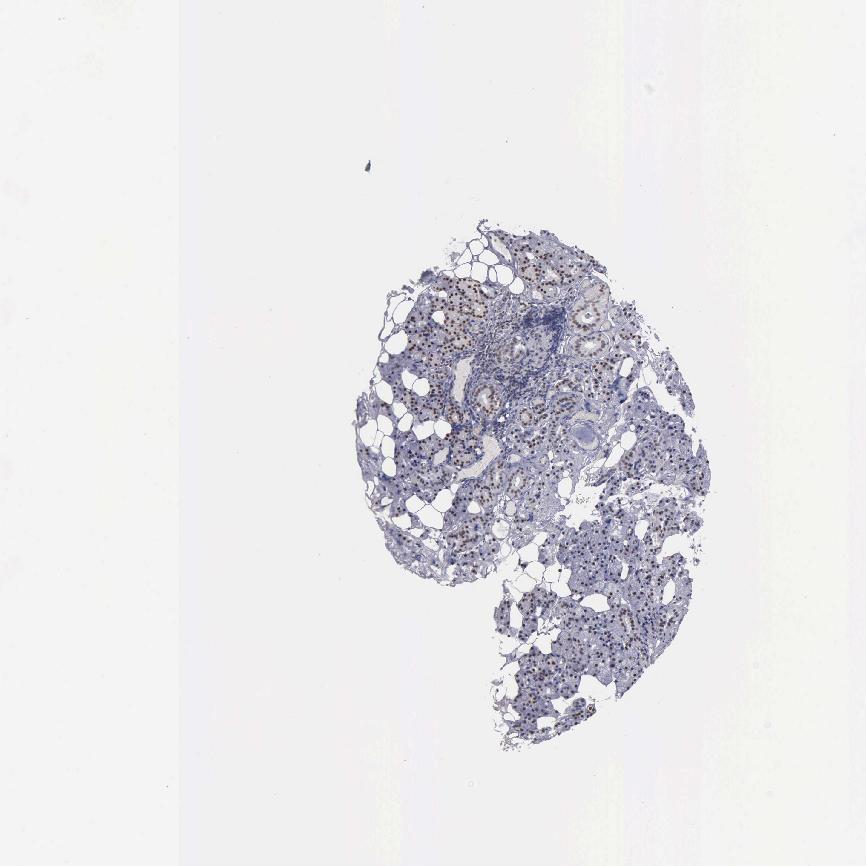

SALIVARY GLAND - Antibody stainingi

Antibody staining in the annotated cell types in the current human tissue is reported as not detected, low, medium, or high, based on conventional immunohistochemistry profiling in selected tissues. This score is based on the combination of the staining intensity and fraction of stained cells.

Each image is clickable and will lead to virtual microscopy that enables deeper exploration of all samples and also displays staining intensity scores, fraction scores and subcellular localization as well as patient and tissue information for each sample.

Antibody CAB000350

Glandular cells High